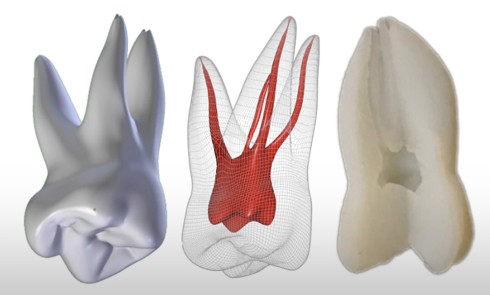

La conduite du traitement endodontique est un domaine où cette analyse en 3D prend toute son importance. Selon Karabucak et al. (2016) [4], le risque de persistance de pathologie péri-apicale est multiplié par quatre lorsqu’un canal a été oublié. Des radiographies excentrées augmentent les chances de découvrir un canal supplémentaire, et ces chances sont…